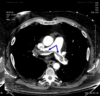

squamous cell cancer

which cells does this occur in? where is it located? how can you dianose/what is major symtom? what is a random paraneoplastic syndrome associated with this? what is interesting about the metastsis of this? who is this most common in?

MOST COMMON NON-SMALL CELL IN SMOKERS!!!

basal cells of bronchial epithelium

centrally located, frequency hemoptysis and change of cough, CAVITATION

hemoptosis diagnosed with cytology

late metastasis–so if you catch it early in the patient the prognosis is better!

paraneoplastic synderome: hypercalcemia

TX: surgical

adenocarcinoma

what is this the most common of? where does the cancer occur and where does it appear? what does it metastasize to? what is the treatment? what are two paraneoplastic syndromes? what can you get it from? smokers or nonsmokers?

most common bronchogenic CA

common in non-smokers

peripheral, lung parenchyma

originates in the mucous glands of tracheobrachial tree and appears in the periphreay of lung

moderate growth and metastatic rate

NON SMOKERS, can get from ASBESTOS!!!

paraneoplastic syndrome: thrombophlebitis, PTH-rp

TX: surgical